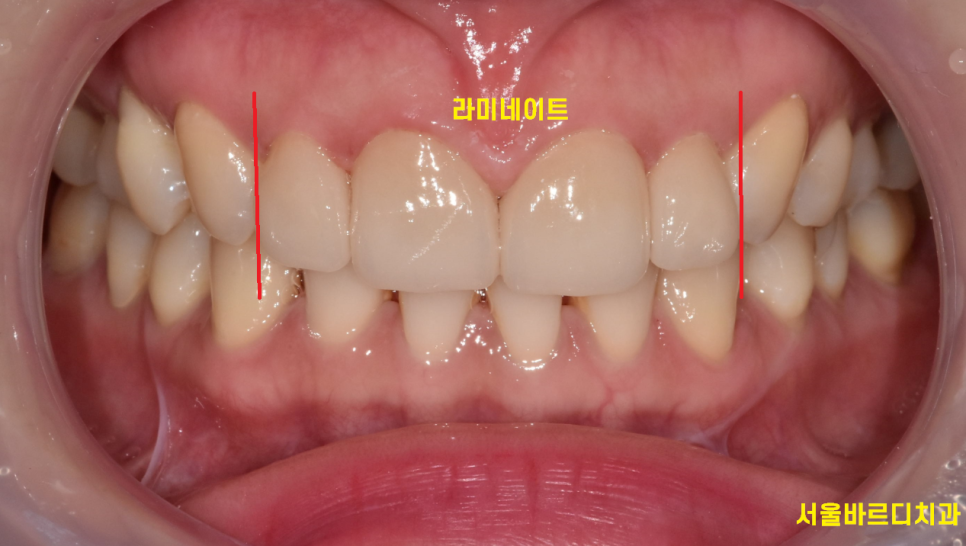

환자분은 바로 옆 대문니가 크다 보니

치아가 각도상 비틀어져 있어서

유독 작게 보이네요.

반대편 같은 치아의 경우 각도는 제대로 되었지만

이 역시 왜소치에 속합니다.

x-ray를 보니 송곳니 ,

맨 앞 대문니에 비해 크기가 작은게 눈에 보이실겁니다.

이러다보니 작은 치아 콤플렉스가 있으셨다고 합니다ㅠㅠ

다른 부위도 아닌 앞니라

사람들에게 잘 보일 수 있는 부분이니까요~

이럴 경우 최적의 해결방법은??

왜소치 라미네이트